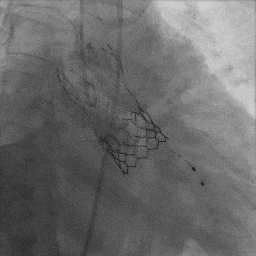

主动脉根部造影

S3定位及植入

最终造影

(1)TAVR in TAVR中需重点评估冠脉风险,相较于自体瓣膜评估,瓣中瓣植入过程中,需重点关注几个指标(图6):coronary risk plane(CRP),New-skirt Plane(NSP),VTA:VTC,VTAoS,VTSTJ。主要原因在于人工瓣膜将会形成新的封堵平面,术前评估中需重点关注。

(2)需熟悉人工瓣膜挂瓣高度,本例患者植入启明瓣膜,其封堵挂瓣高度为Node 3至Node 6。

(3)球扩瓣不同植入深度,将影响第一个瓣膜封堵区域(图8),本例患者在不影响二尖瓣前叶情况下,采用较深的植入深度:node 3-4之间(图9),最大限度规避冠脉堵塞风险,术后结果满意。